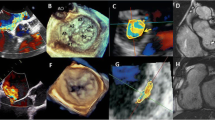

LGE CMR is considered the reference standard to quantify myocardial replacement fibrosis and scar. The increased extracellular space and decreased capillary density of the fibrous tissue result in increased volume of distribution and prolonged wash-out of gadolinium in comparison to the normal myocardium [13]. 10–20 min after intravenous administration of gadolinium, inversion recovery images are acquired in mid to late diastole. The inversion time is chosen to null the normal myocardium and provide the best tissue contrast between fibrous tissue, which appears bright, and normal myocardium, which appears black. Distinct patterns of LGE have been described in various cardiac diseases and associated with adverse prognosis [14,15,16,17,18,19] (Fig. 2).

Patterns of late gadolinium enhancement (LGE). A shows no LGE, no focal replacement fibrosis. B–E demonstrate different patterns of non-infarct myocardial fibrosis: B diffuse patchy LGE of the anterior and lateral wall (arrows); C focal nodular LGE of the inferior wall (arrow); D focal LGE of the anterior and inferior right ventricular insertion points (arrows) and E linear midwall septal LGE with additional foci at the right ventricular insertion points (arrows). In F, typical infarct-type subendocardial LGE distribution is shown (arrows)

LGE, myocardial replacement fibrosis, is detected in 19–62% of patients with severe AS [19, 32, 47, 48]. Two forms of LGE can be observed: the ischemic and the non-ischemic pattern. The ischemic pattern is characterized by subendocardial LGE along specific coronary artery territories whereas in the non-ischemic pattern the distribution of LGE can be diffuse, (multi)focal or linear, confined or patchy, and is predominantly located in the midwall myocardial layer and does not correspond to a specific coronary artery territory (Fig. 2) [19, 32, 47, 48]. The presence and the extent of LGE have been associated with increased LV mass, worse LV ejection fraction, the presence of symptoms, markers of myocardial injury such NT-pro-brain natriuretic peptide and high-sensitivity cardiac troponins and ECG strain (Table 2) [19, 32, 45, 46, 48, 49]. However, LGE was not significantly associated with transaortic gradients or the aortic valve area, common indices of AS severity [19, 32, 48], suggesting that there is different individual susceptibility to develop LV hypertrophy and myocardial fibrosis, likely influenced by multiple factors such as advanced age, male sex, obesity and certain genetic variants [50].